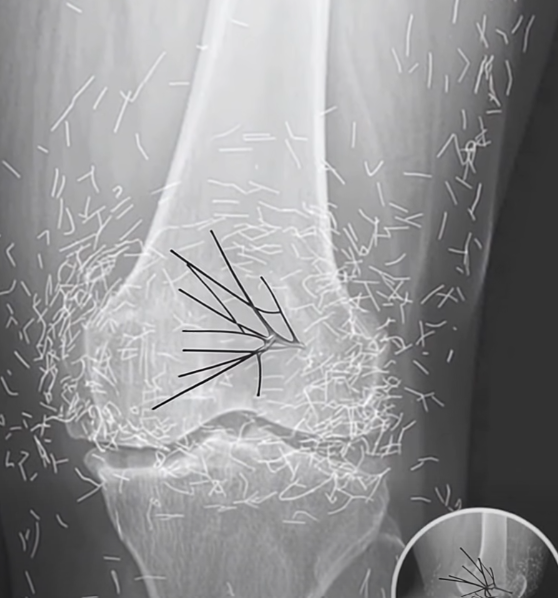

Routine Knee X-Ray Reveals an Unusual Finding

A 65-year-old woman in South Korea went to the hospital expecting routine arthritis tests, only to be met with an extraordinary discovery. Instead of the usual signs of joint wear, her X-ray revealed that her knees were filled with hundreds of tiny gold needles, a finding that astonished both the patient and her doctors. What was intended as therapy had left behind an unexpected medical mystery.